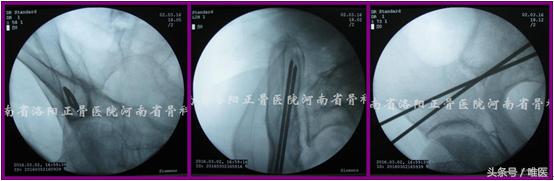

3. 置钉操作步骤

(1)确定进针点 透视出患侧骨盆Teepee像。两枚克氏针十字交叉放置于术区(AIIS尖部稍偏外侧)并调整,直至其交点正好位于Teepee像上“水滴”或“圆锥形帐篷”的中点(拟置入一枚螺钉时)或中点的稍尾端(拟置入两枚螺钉时)。应用亚甲蓝标记克氏针交点所对应的皮肤。于上述皮肤进针点做一长约1.0cm切口并钝性分离至AIIS。(图8)

图8. 确定进针点。

(2)置入导针 沿上述切口置入一枚无螺纹的空心钉导针至AIIS骨质。在骨盆Teepee像上确定针尖在“水滴”或“圆锥形帐篷”内的位置良好后将导针轻浅打入骨质,然后尽可能将导针调整成点状后再继续打入骨内(可保证导针沿安全通道的长轴行进而不会突破其周围骨质)(徒手操作时往往极难实现)。关注导针应避开安全区域的内下方以免置入过长时突入SIJ[17]。(图9)

图9. 置入导针。

(3)导针入位 如导针被成功地调整并维持成点状,则透视患侧的髂骨斜位像并在其监视下将导针打过骨折端至一定长度(避免超出髂骨后部即PSIS、PIIS骨皮质以免突入软组织内),此时导针必定位于髂窝薄弱骨质的尾端,GSN及髋臼头端。如未能将导针调整成圆点,尽管在髂骨斜位上其位置良好,仍需要追加透视患侧髂骨入口位像以确定其位于后部髂骨的内外板之间、IC之前进而避免其突入软组织及SIJ内。(图10)

图10. 导针入位。